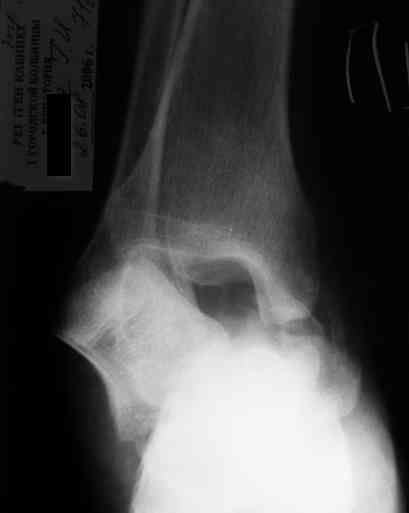

Уважаемый Александр! Как обещал представляю Р-граммы и операционные фото.

Вместе с аваскулярным куском кости устранится субстрат. Надо опасаться не мягких тканей, а плохо кровоснабжаемых. Если после удаления тарана добиться контакта хорошо васкуляризованных пятки и больщшеберцовой, мягкие ткани не давить, чтобы некроза раны не было, то все должно зажить.

Стабильность дает возможность расти сосудам. При хорошем кровоснабжении смежных фрагментов это все, что надо. А здесь есть большой секвестр. Разумно ли ждать, пока он васкуляризуется? Очевидно, без некрэктомии проблему не решить.